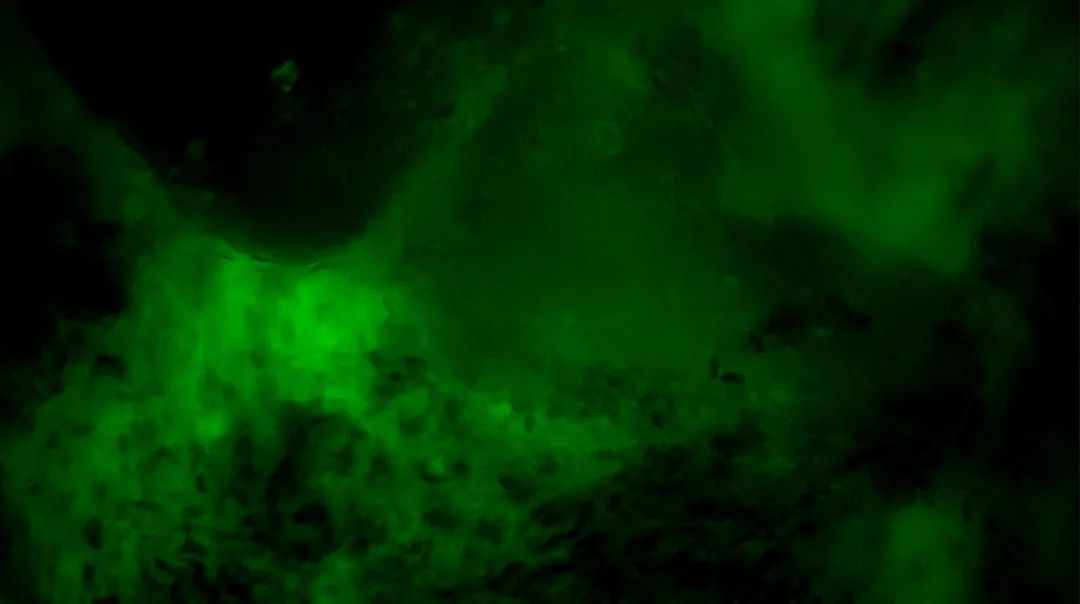

3次切緣掃查的EndoSCell?細(xì)胞圖像

3

陰性,細(xì)胞核形態(tài)正常、分布均勻